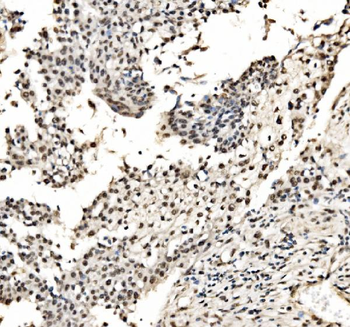

- PPM1D Rabbit Polyclonal Antibody [orb704535]Featured

IF, IHC-Fr, IHC-P

Human, Mouse, Rat

Mouse, Rat

Rabbit

Polyclonal

Unconjugated

100 μl, 50 μl, 200 μl - HSC70 Mouse Monoclonal Antibody [orb704174]Featured